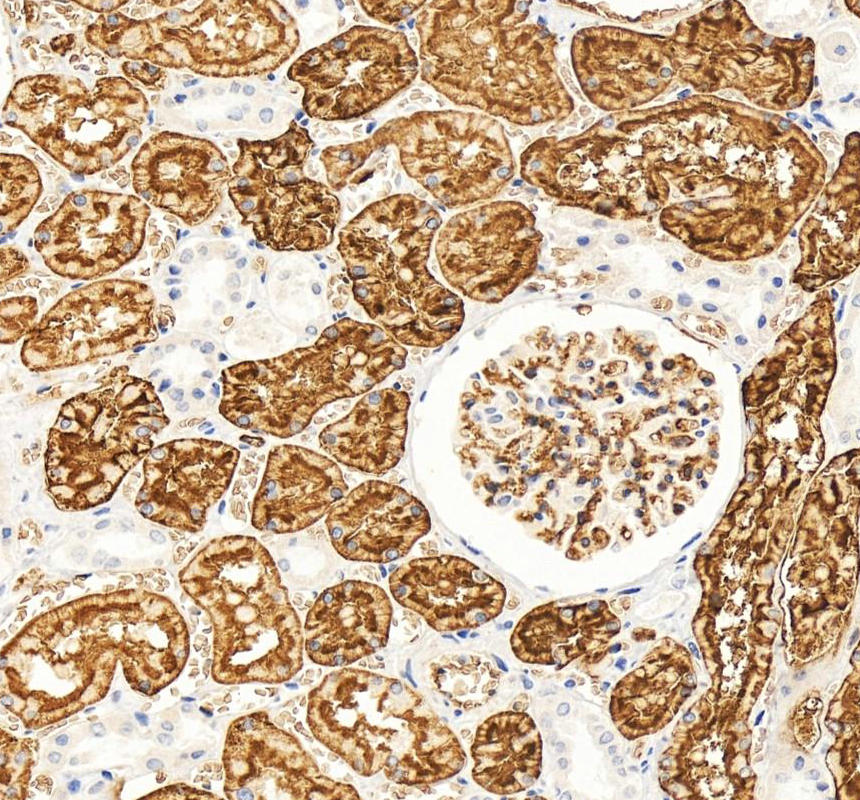

IHC analysis of AQP1 using anti-AQP1 antibody (PB9473).

AQP1 was detected in a paraffin-embedded section of human kidney tissue. The tissue section was incubated with rabbit anti-AQP1 Antibody (PB9473) at a dilution of 1:200 and developed using HRP Conjugated Rabbit IgG Super Vision Assay Kit (Catalog # SV0002) with DAB (Catalog # AR1027) as the chromogen.